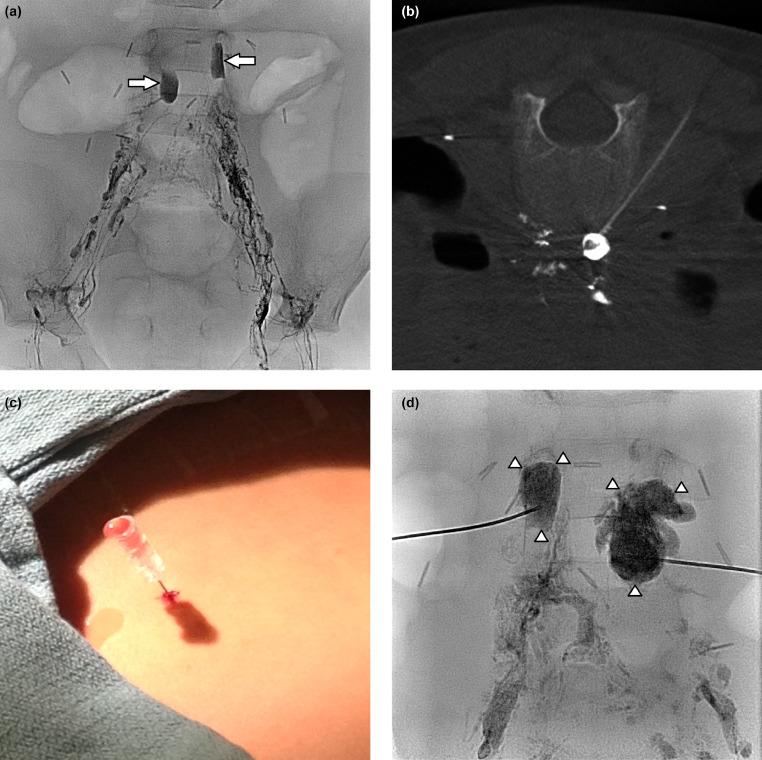

Chylous ascites is a rare, but highly morbid complication of oncologic resection, often associated with retroperitoneal lymphadenectomy. Conservative measures with total parenteral nutrition or lipid-reduced formulas constitute the initial mainstay therapy, but not without risks and failures. This report describes 2 endolymphatic treatment strategies for iatrogenic chylous ascites following neuroblastoma resection. Lymphatic leaks were identified using intranodal lymphangiography, targeted with cone-beam computed tomographic guidance, and embolized with n-butyl cyanoacrylate. There were no adverse outcomes, with complete resolution of chylous ascites and a mean follow-up of 26 months.

乳糜性腹水是肿瘤切除术后一种罕见但严重的并发症,常与腹膜后淋巴结清扫术相关。全胃肠外营养或低脂配方的保守措施是初始的主要治疗方法,但并非没有风险和失败案例。本报告描述了神经母细胞瘤切除术后医源性乳糜性腹水的两种淋巴管内治疗策略。通过节点内淋巴管造影识别淋巴漏,在锥形束计算机断层扫描引导下进行靶向治疗,并使用氰基丙烯酸正丁酯进行栓塞。没有出现不良后果,乳糜性腹水完全消退,平均随访26个月。